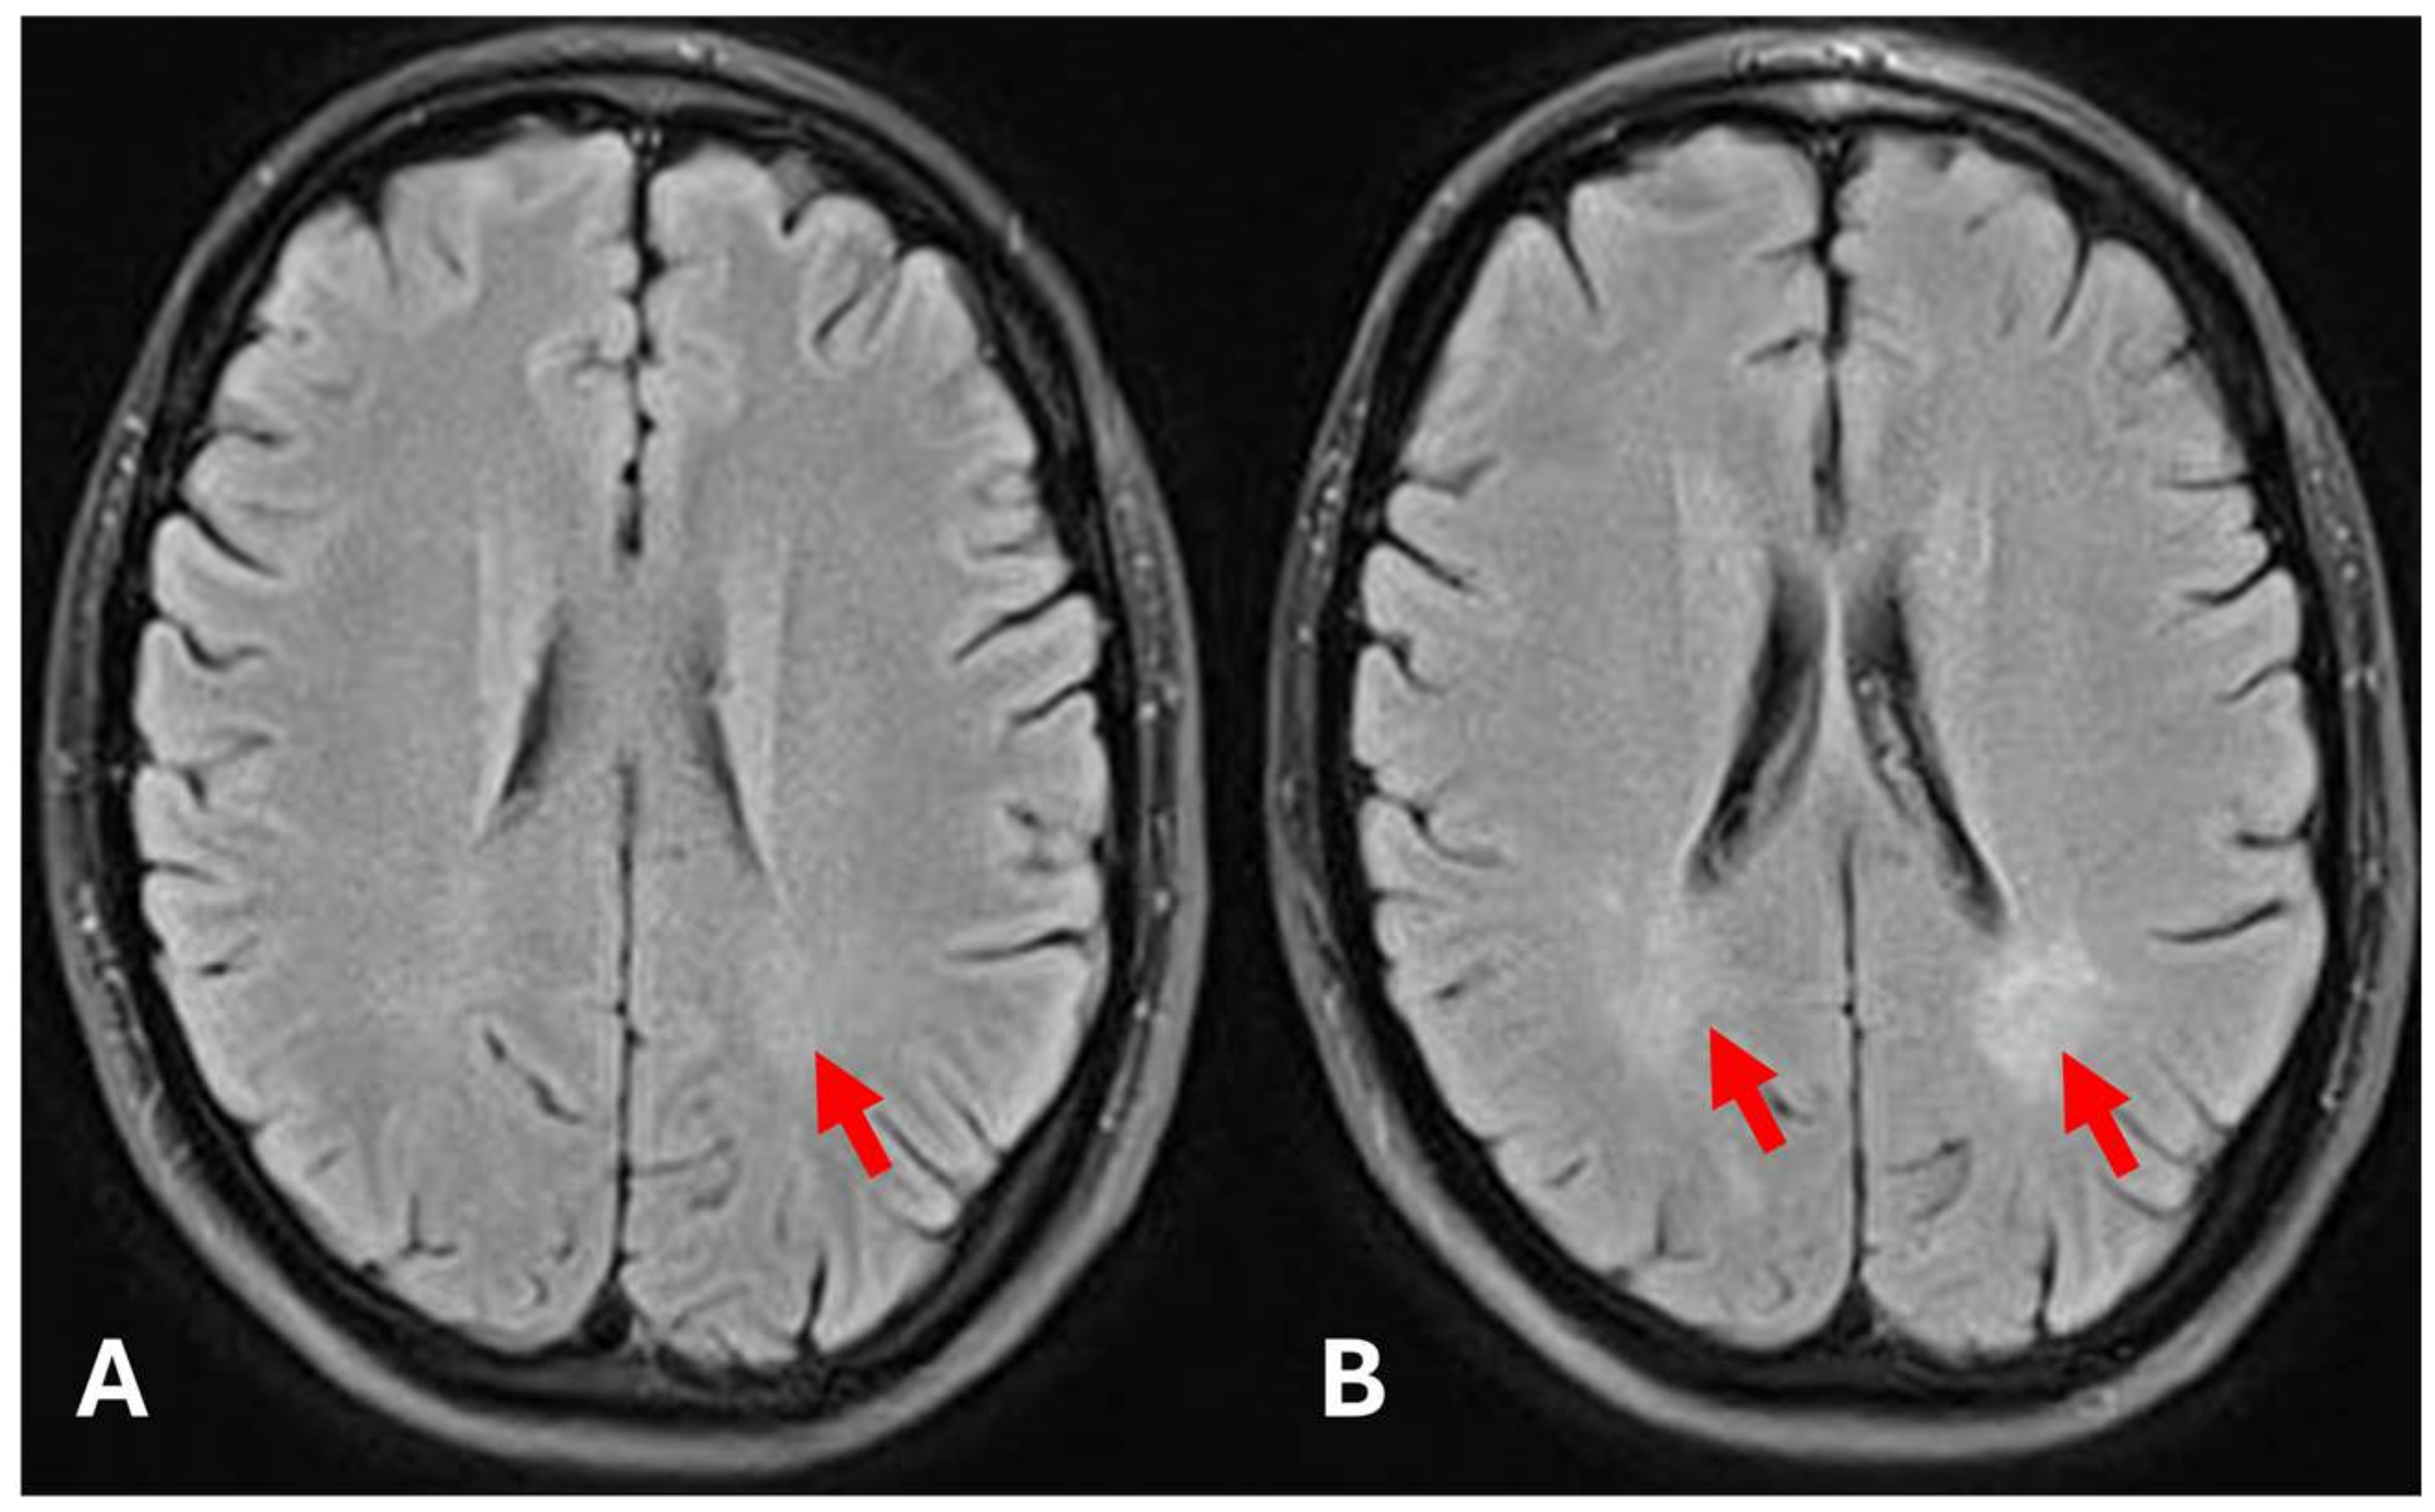

2. Case Presentation